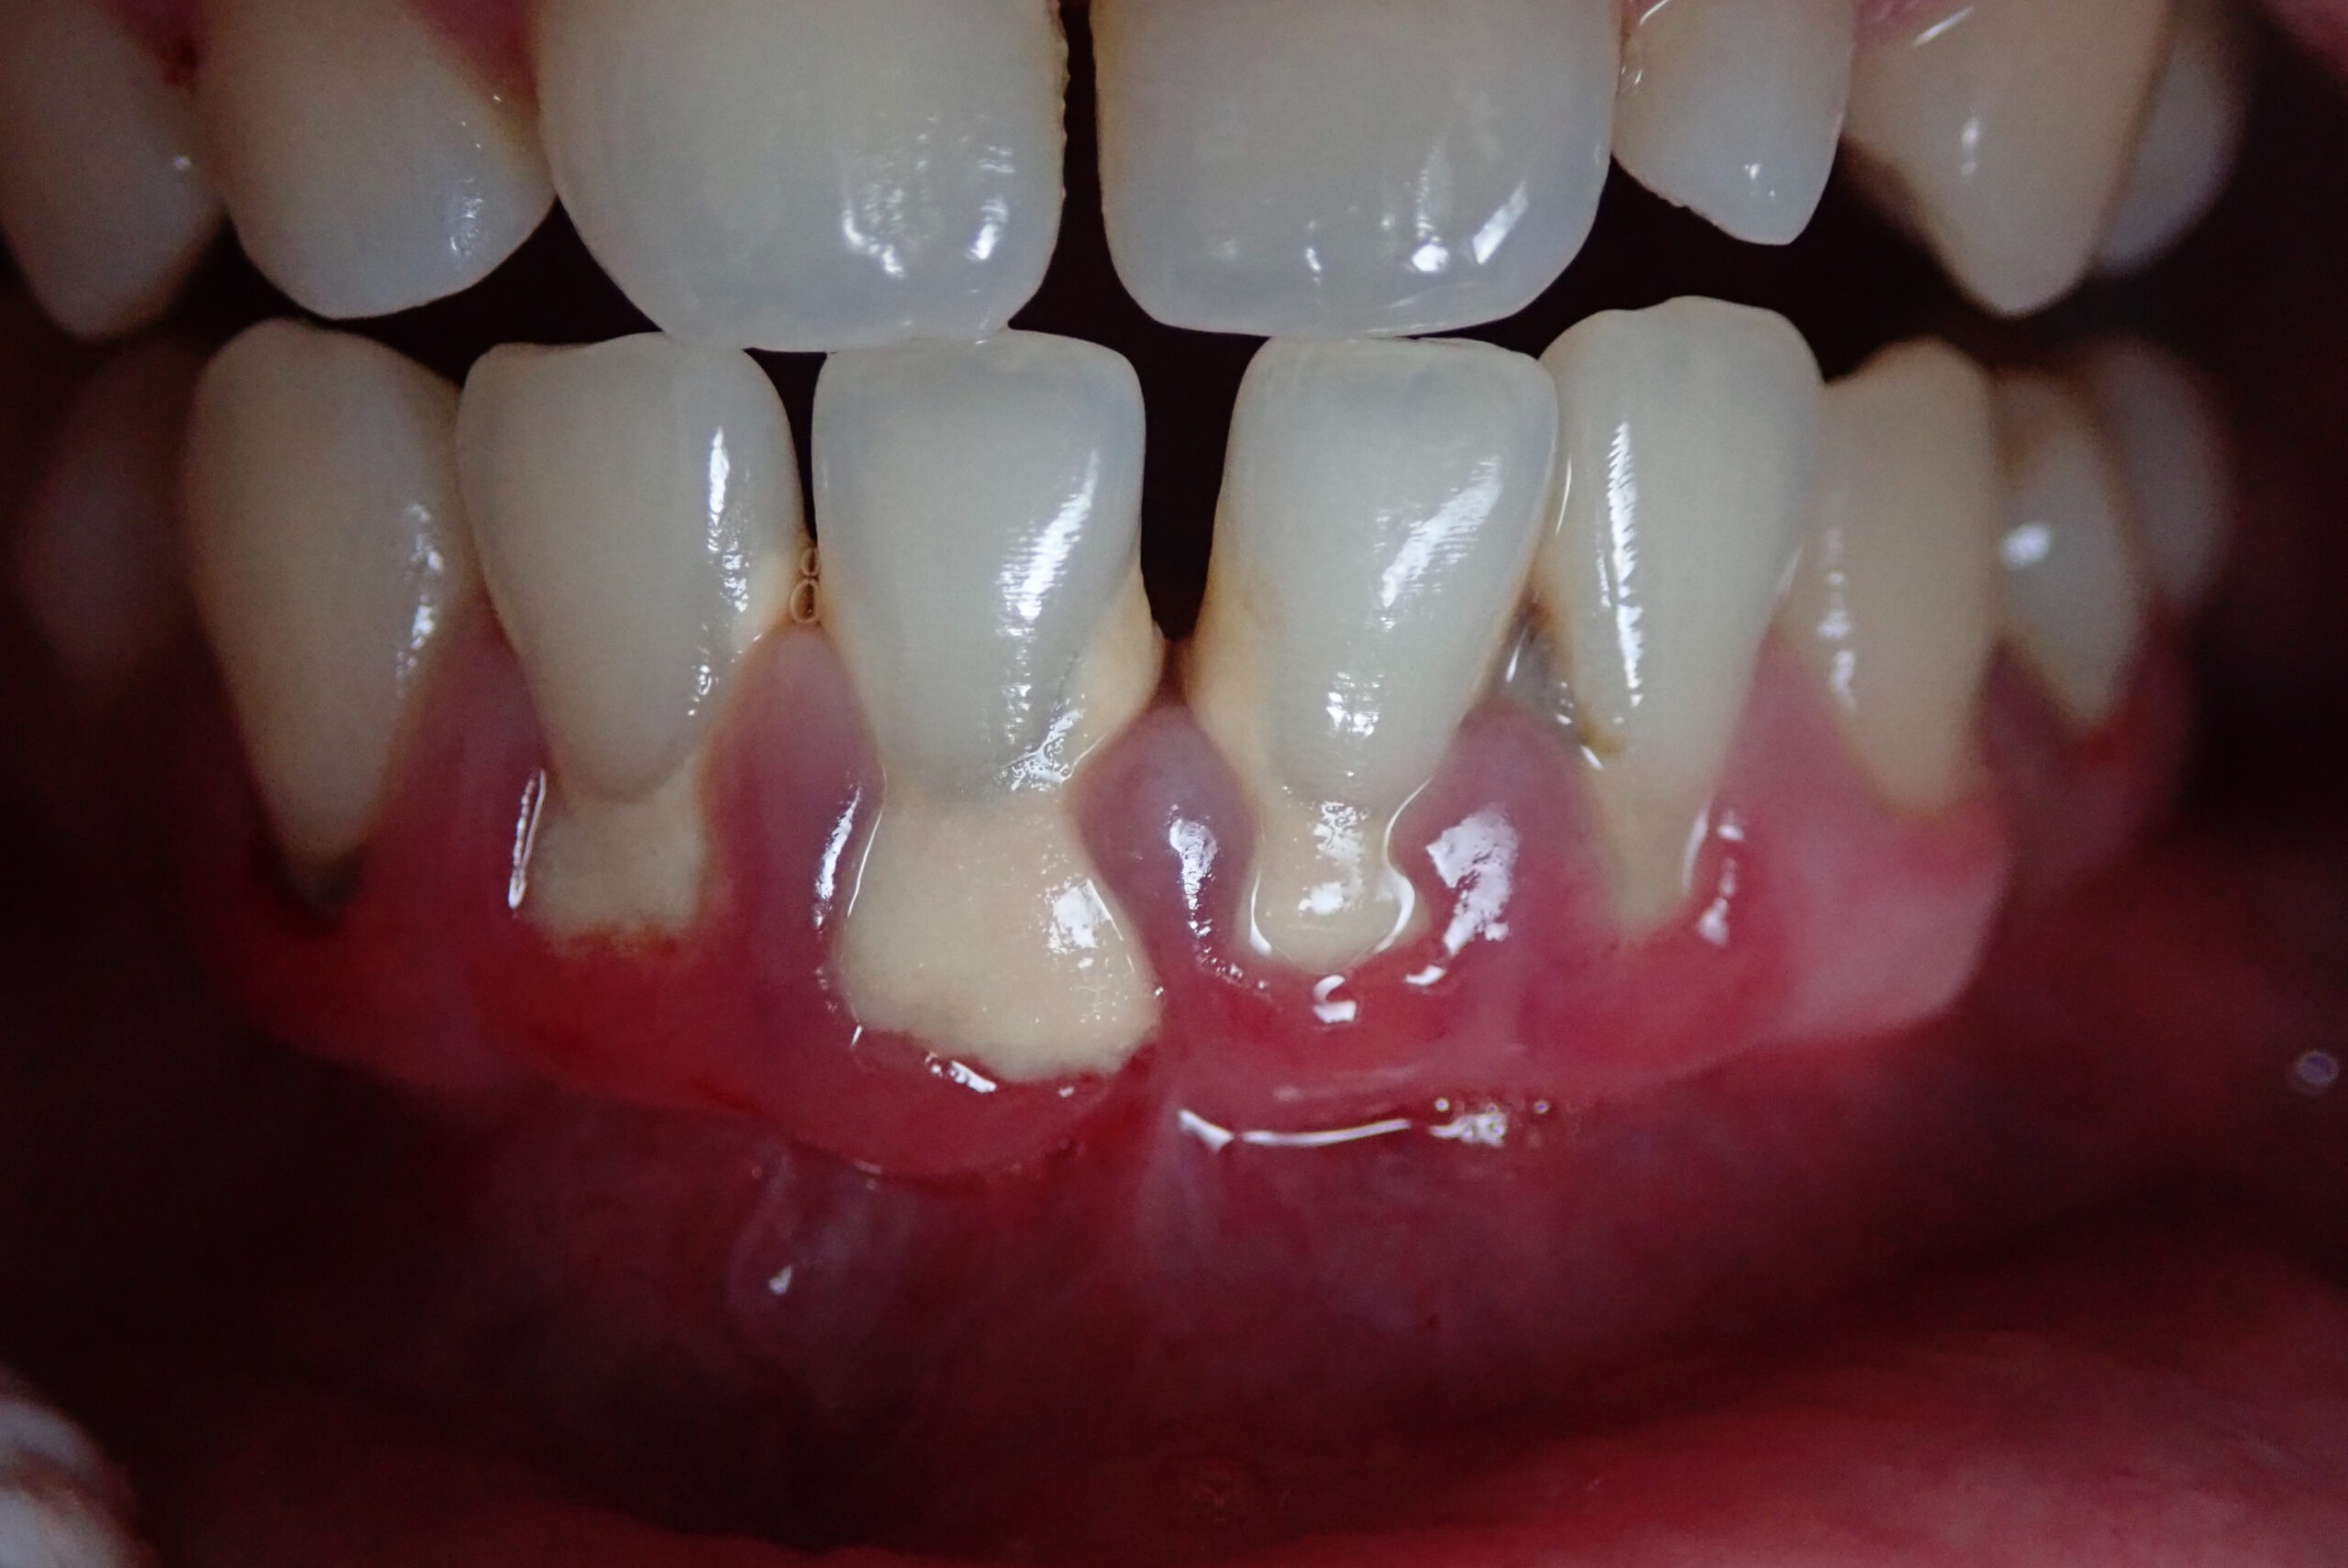

Because gingivitis tends to be painless in its early stages, it is easy to overlook the signals the body is sending. The five most common signs are bleeding gums during brushing, visible gum recession or tissue loss, swelling along the gum line, redness, and persistent bad breath.

Bleeding is the one that most people misread. The natural instinct when gums bleed during brushing is to ease up or stop, assuming the brush is being applied too aggressively. In most cases, bleeding is actually a signal that the area needs more thorough cleaning, not less. Backing off allows plaque to accumulate further and makes the inflammation worse over time.